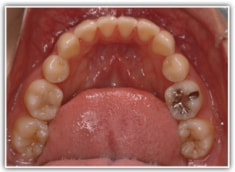

治療前

治療開始時

上下顎とも前突しており、叢生もあります。分析値からも抜歯対象症例です。

検査時パノラマレントゲン

特に小臼歯部に叢生があり、8番(親知らず)も埋伏しています。8番と7番の接触部分に吸収が若干あるような所見が認められます。